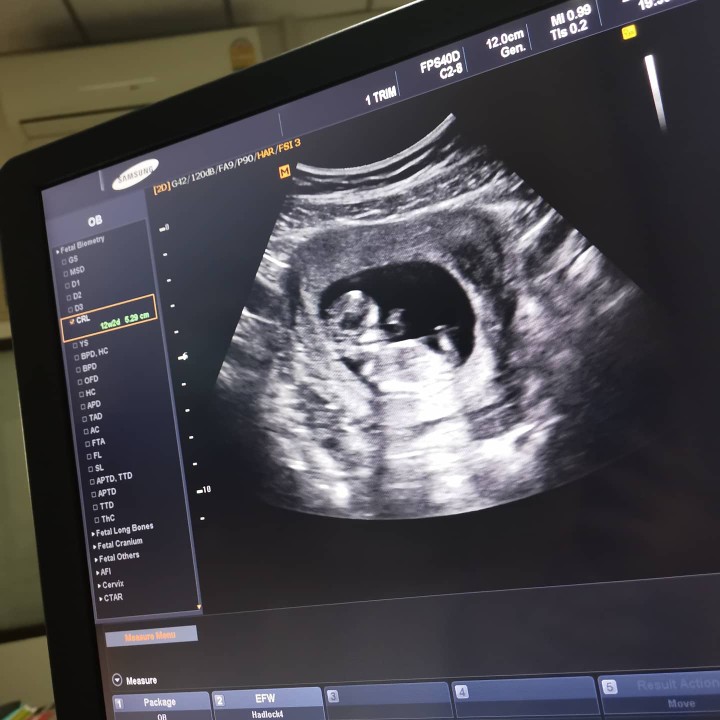

บ้านนี้ตอน 8w4d ค่ะ